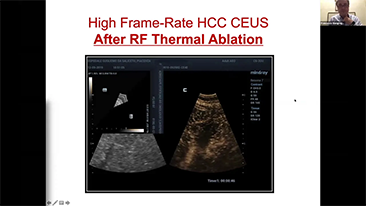

Per le lesioni focali epatiche, come l'emangioma o il tumore al fegato, l'imaging di contrasto a ultrasuoni svolge un ruolo importante. La tecnologia di imaging di contrasto Ultra-wideband non-linear UWN+ consente di ottenere una migliore penetrazione, un rapporto contrasto-tessuto pi├╣ elevato con un indice meccanico pi├╣ basso e un'osservazione del tempo di perfusione pi├╣ lunga.